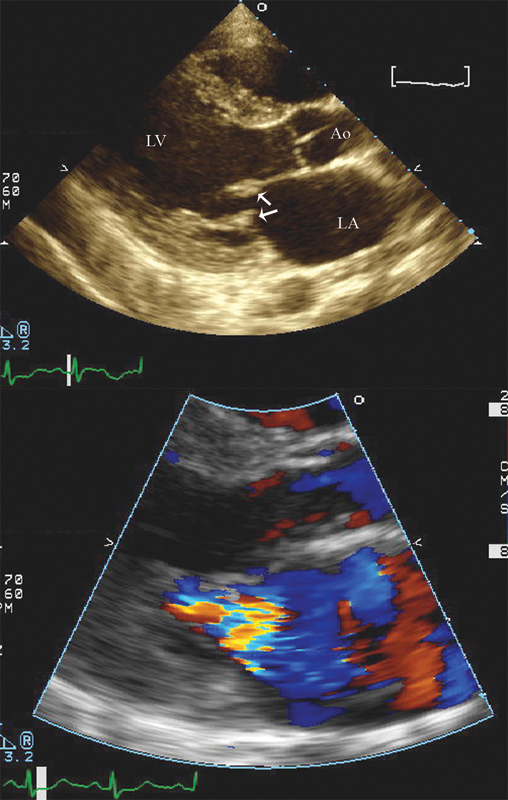

فحوصات تشخيصية لبعض امراض القلب والشرايين التاجية